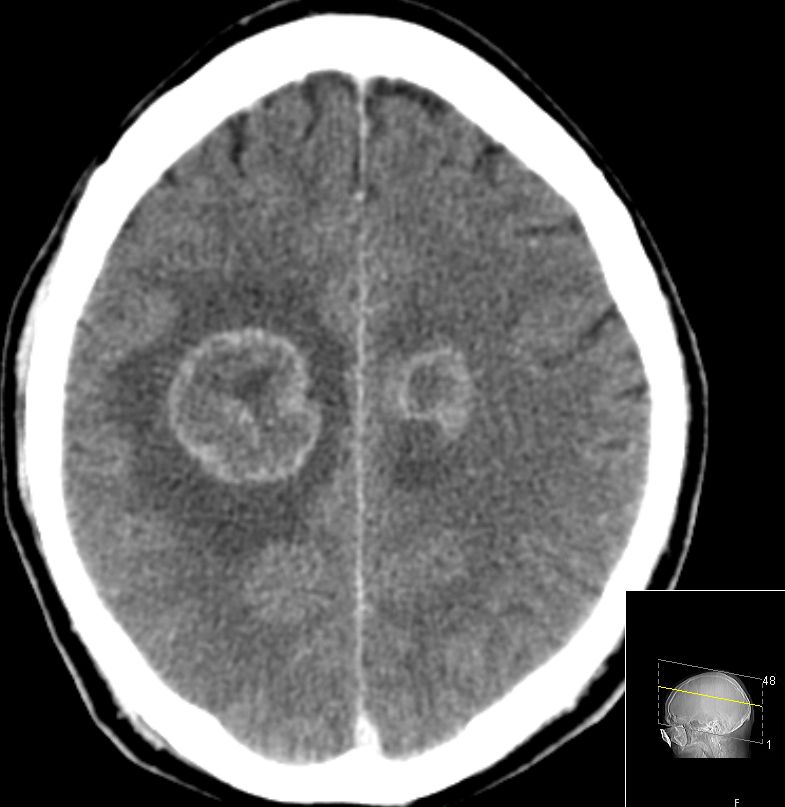

| CT: multiple Hirnmetastasen | Adenokarzinom der Lunge. CT-Untersuchung des Hirns mit Kontrastmittel. | |||

![]() |

![]() | |||